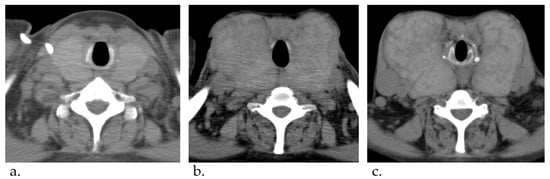

A Case of Giant Goiter Associated with Airway Stenosis Caused by Long-Term Intravenous Epoprostenol Therapy for Idiopathic Pulmonary Arterial Hypertension

Nishiura, K.; Nakazato, K.; Yokokawa, T.; Suzuki, Y.; Kurosawa, Y.; Wada, K.; Shimizu, T.; Oikawa, M.; Kobayashi, A.; Sugimoto, K.; et al. A Case of Giant Goiter Associated with Airway Stenosis Caused by Long-Term Intravenous Epoprostenol Therapy for Idiopathic Pulmonary Arterial Hypertension. J. Clin. Med. 2023, 12, 6359. https://doi.org/10.3390/jcm12196359